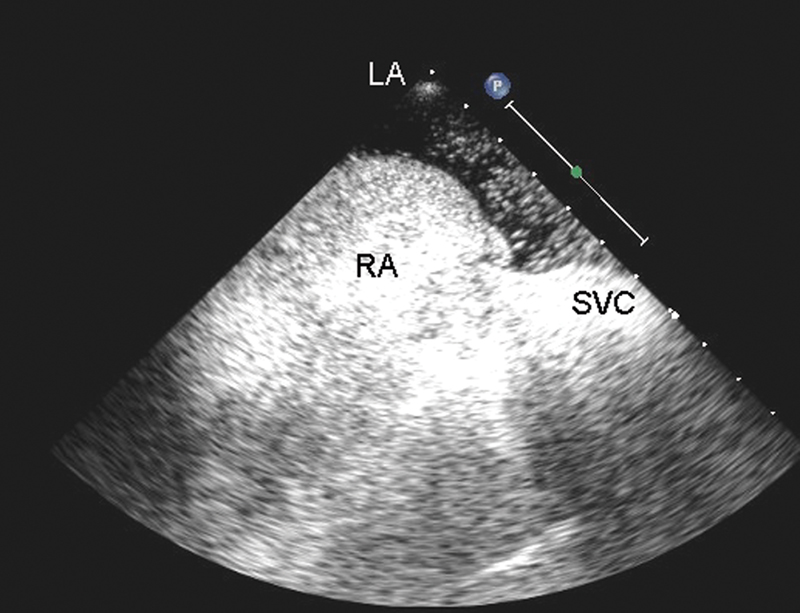

فحوصات تشخيصية لبعض امراض القلب والشرايين التاجية